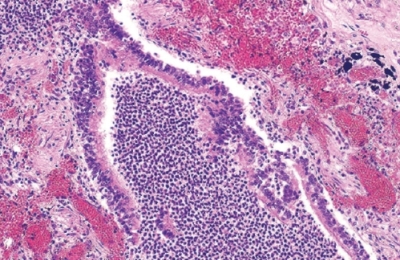

- лейкоз – опухоли системы крови, которые обуславливают язвенное поражение слизистых оболочек;

Реже причинами, когда появляются гнойнички и белые точки, являются грибки. Чаще всего они вызваны Candida albicans, но в роли возбудителей могут быть и другие виды.

Именно с ними и связаны неудачи в фармакологической терапии. Дифференциальный признак диагностики – это то, что при кандидозе налет очень плохо удаляется. Внешне он напоминает творог.